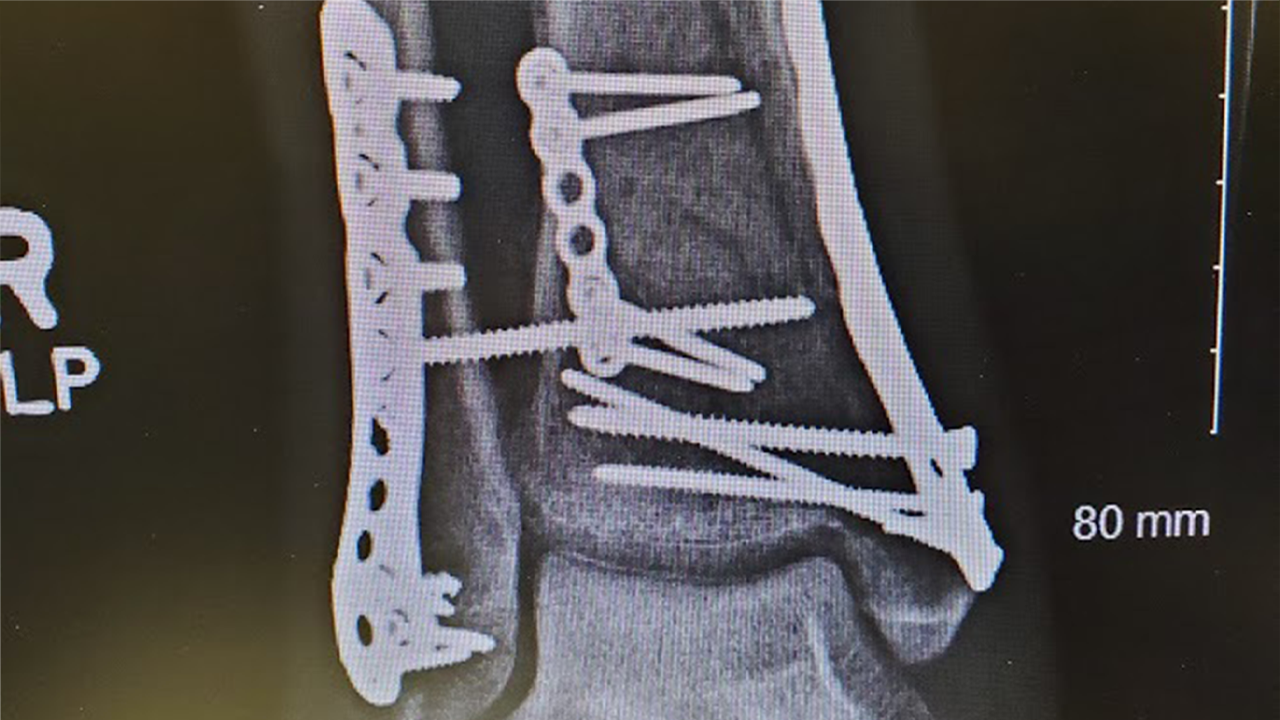

In order to reconstruct Dr. Sanjay’s entire lower leg and ankle, Dr. Dixon performed an open reduction and internal fixation by creating four incisions and inserted three plates and 17 screws into his tibia and fibula.

“Dr. Sanjay’s injury is complex because he damaged the largest weight-bearing part of the ankle,” Dr. Dixon explained. “This injury is often initially fixed by an orthopaedic surgeon, but then the care is taken over by a trauma surgeon or foot and ankle surgeon who has the appropriate skill set to perform the definitive surgery.”